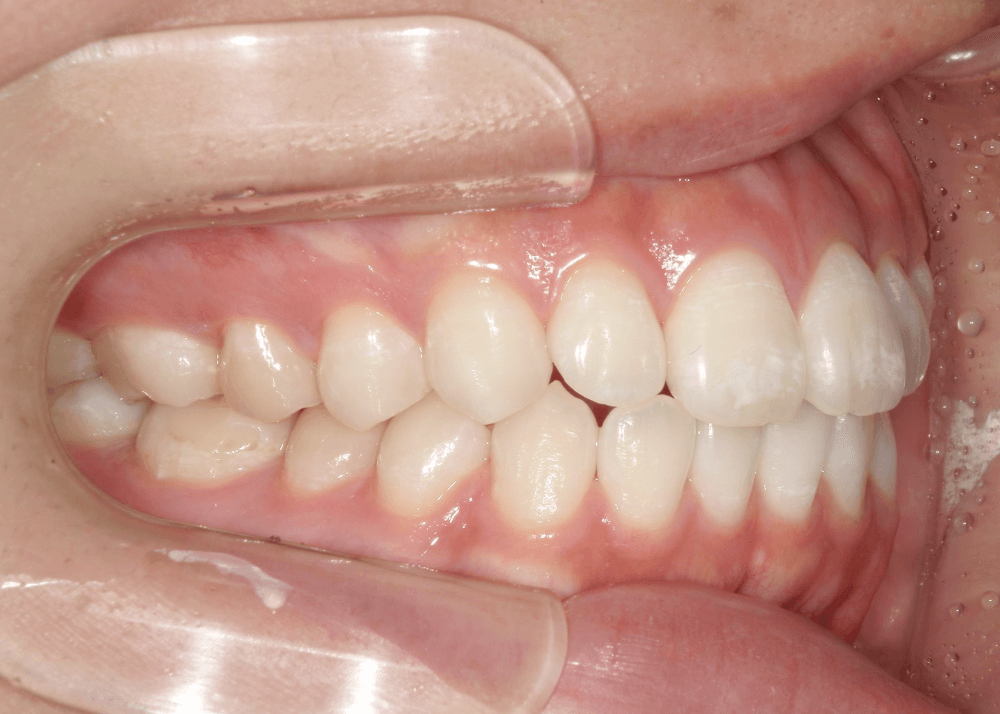

<初診時>

一見すると大きなガタガタはなく、歯並び自体は比較的きれいに整っているように見えます。

角度を変えて確認すると、上の前歯が前方に突出しており、上下の前歯がしっかり噛み合っていない状態(前歯部に隙間)が認められました。

このように、歯列の乱れは軽度である一方、前歯の前突および口元の突出感が認められました。